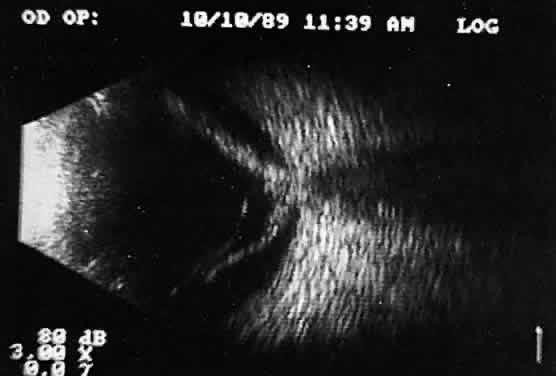

Choroidal malignant melanoma, perhaps the most widely studied intraocular mass lesion, has the most reproducible and reliable A-scan pattern. Usually, the initial echo seen in A-scan is a high-amplitude spike secondary to the strong vitreoretinal surface echo overlying the tumor mass. Once the examining sonic beam has passed into the tumor tissue, a rapidly declining amplitude cadence is noted, a consequence of increasing ultrasonic tissue homogeneity. Clinical knowledge of the typical microscopic tumor pattern of tightly packed, homogeneous small cells makes anticipation of relatively low reflectivity possible (Fig. 10). This same low-amplitude reflectivity in B-scan imaging produces a picture that makes the melanoma mass appear hollow. Often, tumor-infiltrated choroid also appears dark (Fig. 11). This change in the normally highly reflective choroidal tissue is widely but inaccurately called choroidal excavation. The terms “hollowing” and “choroidal excavation” are misleading because these tumors are not hollow and the choroid is not excavated. Nevertheless, these terms have been used so frequently in past literature that any change in vocabulary is unlikely.

Fig. 10. Contact B-scan and simultaneous A-scan: choroidal malignant melanoma. Note the strong initial echo from the overlying retinal tissue, followed by a rapid decline in A-scan echo amplitude within the deeper tumor tissue, a consequence of increasingly homogeneous tissue. High reflectivity is again seen at the level of the sclera and orbit.

Fig. 11. Contact B-scan: malignant melanoma, demonstrating hollowing and choroidal excavation.